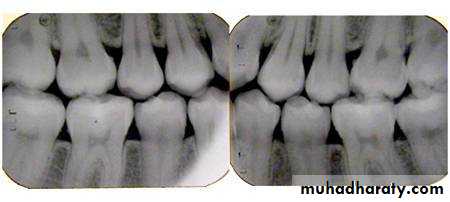

Bitewing radiograph. This radiograph shows (1) large occlusal caries, (2) radiolucent lines or mach band effect (an optical illusion caused by overlapped enamel), (3) interproximal caries, and

(4) cervical burnout

This radiograph shows (1) radiolucent restorations (composites) on the mesial surface of the lateral incisor and distal surface of the central incisor. Note that under both restorations is a base of radiopaque material. (2) The radiolucencies on the mesial surfaces of both central incisors are carious lesions.

Restorative Materials & Decay

Retention pins. (1) Radiopaque pins help retain the radiolucent composite restorations. (2) Small radiopaque amalgam restorations.